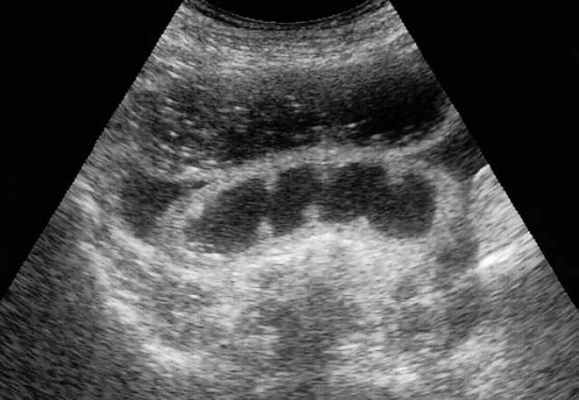

УЗД признаки тонкокишечной непроходимости

Основные УЗ-признаки при непроходмости- это визуализация расширенных петель тонкой кишки, сниженная перистальтика, свободная жидкость между петлями (танга) и в брюшной полости. Также УЗИ иногда позволяет обнаружить причину обструкции, например, опухоль, утолщение стенок терминального сегмента подвздошной кишки при болезни Крона и т.д. УЗИ может решить диагностическую дилемму при неоднозначных рентгенологических признаках на обзорной рентгенограмме брюшной полости. Лимит метода заключается в низкой специфичности при оценки состояния брыжейки, а также зависимость качества диагностики от конституции пациента и опыта оператора.

примеры сонограмм с расширенными петлями тонкой кишки

УЗИ позволяет прекрасно лоцировать свободную жидкость в брюшной полости